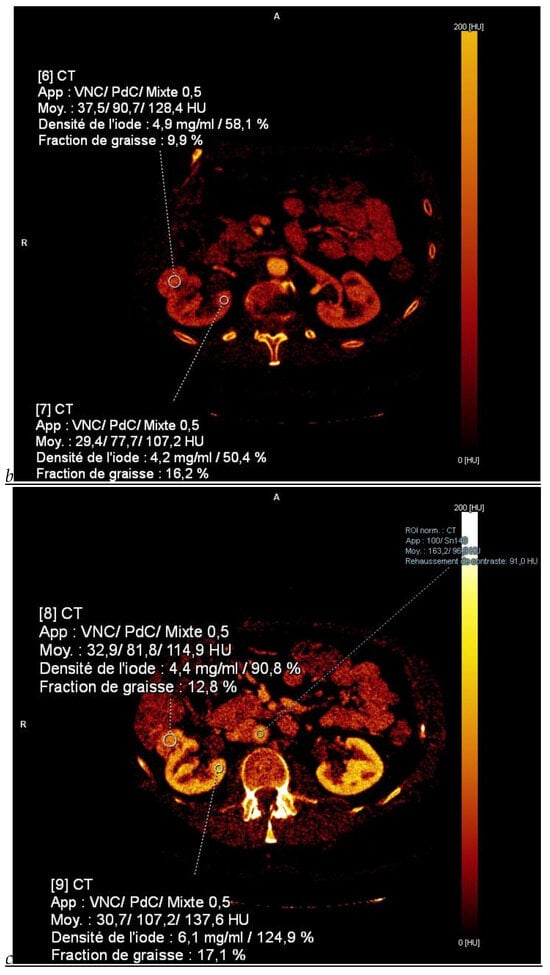

Figure 1.

Dual-energy CT aspect of a hypervascularized clear cell renal cell carcinoma of the upper pole of the right kidney. (a) Virtual unenhanced image. Note the presence of a solid exophytic renal mass in the upper pole of the right kidney. (b) The lesion enhances during the corticomedullary phase; measurement of the iodine concentration of the lesion (4.9 mg/mL) compared to that of the renal cortex (4.2 mg/mL) during the corticomedullary phase. (c) Monoenergetic image obtained at 40 keV during the nephrographic phase. Note the decrease in iodine concentration of the lesion (4.42 mg/mL) compared to that of the renal cortex (6.1 mg/mL). (d) Monoenergetic image obtained at 70 keV during the excretory phase. Compared to the monoenergetic image at 40 keV, the contrast between the lesion and the adjacent renal cortex is reduced. Note the washout of the lesion (iodine content: 1.8 mg/mL).